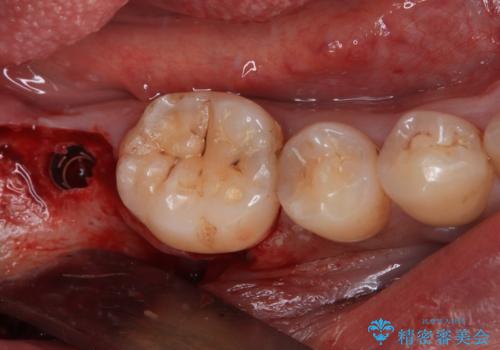

部分矯正で咬み合わせを改善 奥歯のインプラント治療

- 左下欠損部のインプラント治療を希望して来院された患者様です。

左下の欠損部を長期間欠損を放置していたことで、咬み合う上の奥歯が動いてしまっていたので、まずは上顎奥歯の部分矯正を行うこととしました。

理想的な咬み合わせに改善した上で、インプラント補綴治療を行うこととしました。

部分矯正を行ったこと治療期間は長くなりましたが、違和感のない咬み合わせを達成することができました。